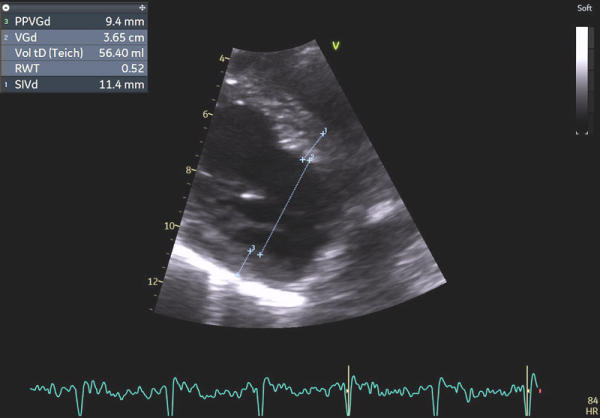

Image 1 : échocardiographie 2D en incidence parasternale grand axe : mesures des parois du ventricule gauche (VG)

En effet, c’était le diagnostic à éliminer en priorité devant les symptômes présentés par la patiente avec un ECG légèrement microvolté et des éléments évocateurs d’une amylose cardiaque à l’échocardiographie : hypertrophie VG très minime mais > 10 mm chez une femme (> 11 mm chez un homme) (cf Vidéo 1 et Image 1), hypertrophie VD à 6 mm (>5 mm) (cf Image 9) et l’altération des strains longitudinaux basaux à l’AFI après valeurs préservées à l’apex (cf Image 7).